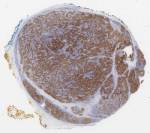

Sections of the mass demonstrated nests and cords of large pleomorphic cells with vesicular nuclei, prominent nucleoli, moderate amounts of eosinophilic cytoplasm, and indistinct cell borders. A prominent lymphoid infiltrate, composed of small mature-appearing lymphocytes with follicle and germinal center formation, was present in and around the aggregates of large pleomorphic cells (Figures 1 and 2). Mitotic figures were readily identifiable (Figure 3). Immunohistochemical staining for AE1/AE3 was positive in the large pleomorphic cells (Figure 4). Synaptophysin and p40 were negative while CD45 was positive only in the lymphoid infiltrate (Figure 5). Epstein-Barr virus-encoded RNA by in situ hybridization (EBER ISH) was negative.

Figure 1: Low magnification view of the tumor’s solid growth pattern with a prominent admixed lymphoid infiltrate (5x)

Figure 4: Cytokeratin cocktail AE1/AE3 was positive in the large pleomorphic cells (5x)